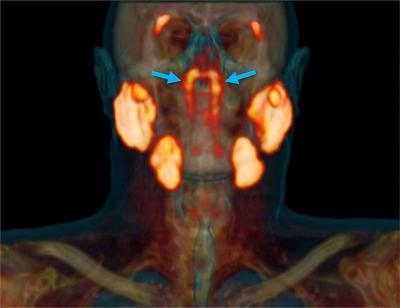

Researchers at the Netherlands Cancer Institute have identified a set of salivary glands deep in the upper part of the throat and have named them “tubarial salivary glands”.

The newly discovered glands are about 1.5 inches (3.9 centimeters) in length on average and are located over a piece of cartilage called the torus tubarius, Livescience reported. According to the researchers, the glands probably lubricate and moisten the upper throat behind the nose and mouth.

The new organ was discovered while scientists were studying prostate cancer cells using PSMA PET-CT technology — a combination of CT scans and positron emission tomography (PET) — which is good in detecting salivary gland tissues. In this technique, a radioactive “tracer” is injected into the patient that binds to the protein PSMA, which is elevated in prostate cancer cells.